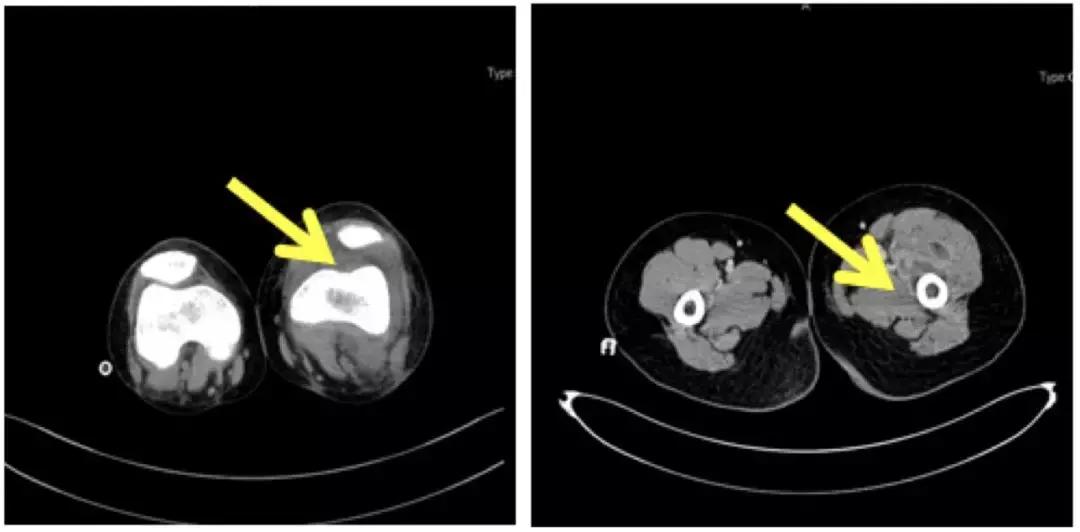

*左侧膝关节 髋关节CT

多学科MDT(呼吸科+骨科+放射科):左侧膝关节软组织肿胀,关节囊及髌上囊积液,关节腔积脓?左侧股骨上段周围软组织肿胀,骨干周围软组织内见多个囊片状低密度影,考虑脓肿可能;